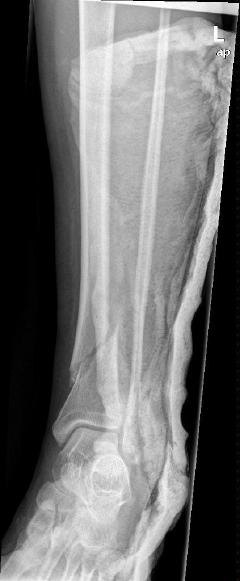

Περίπτωση 2ου ασθενούς

Τα εν λόγω κατάγματα είναι αρκετά συνηθισμένα και συχνά συμβαίνουν μετά από τροχαία ατυχήματα ή πτώση από ύψος. Παρατηρείται εξαιρετικά μεγάλη ποικιλία στη μορφή τους, κατα κανόνα όμως είναι σοβαρά και πολλές φορές ανοικτά – δηλ με τραύμα στο σημείο του κατάγματος – κάτι που αυξάνει τον κίνδυνο λοίμωξης και επιβαρύνει την πορεία της θεραπείας. Στα κατάγματα των άνω άκρων ενδέχεται να υπάρξει και τραυματισμός νεύρων, που χρειάζεται επίσης αντιμετώπιση.

Με τα σύγχρονα μέσα που διαθέτουμε, όλα σχεδόν αυτά τα κατάγματα πρέπει να αντιμετωπίζονται χειρουργικώς. Υπάρχει πληθώρα υλικών οστεοσύνθεσης (πλάκες διαφόρων τύπων, ενδομυελικοί ήλοι, συστήματα εξωτερικής οστεοσύνθεσης) που είναι διαθέσιμα και επαφίεται στην εμπειρία του χειρουργού η επιλογή.

Όλες οι φωτογραφίες ολες προέρχονται από το προσωπικό αρχείο του κου Μ. Τυλλιανάκη